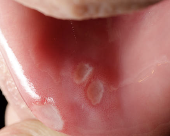

3. 압박성 궤양 (Pressure sore)

틀니가 너무 꽉 끼거나 헐렁해져 생기는 구강 내 궤양, 그냥 방치하면 감염 위험도 있어요.

주요 증상

- 틀니 닿는 부위에 국소적인 궤양이나 붉은 반점

- 씹을 때 찌릿한 통증

- 틀니를 뺀 후에도 아픔이 지속됨